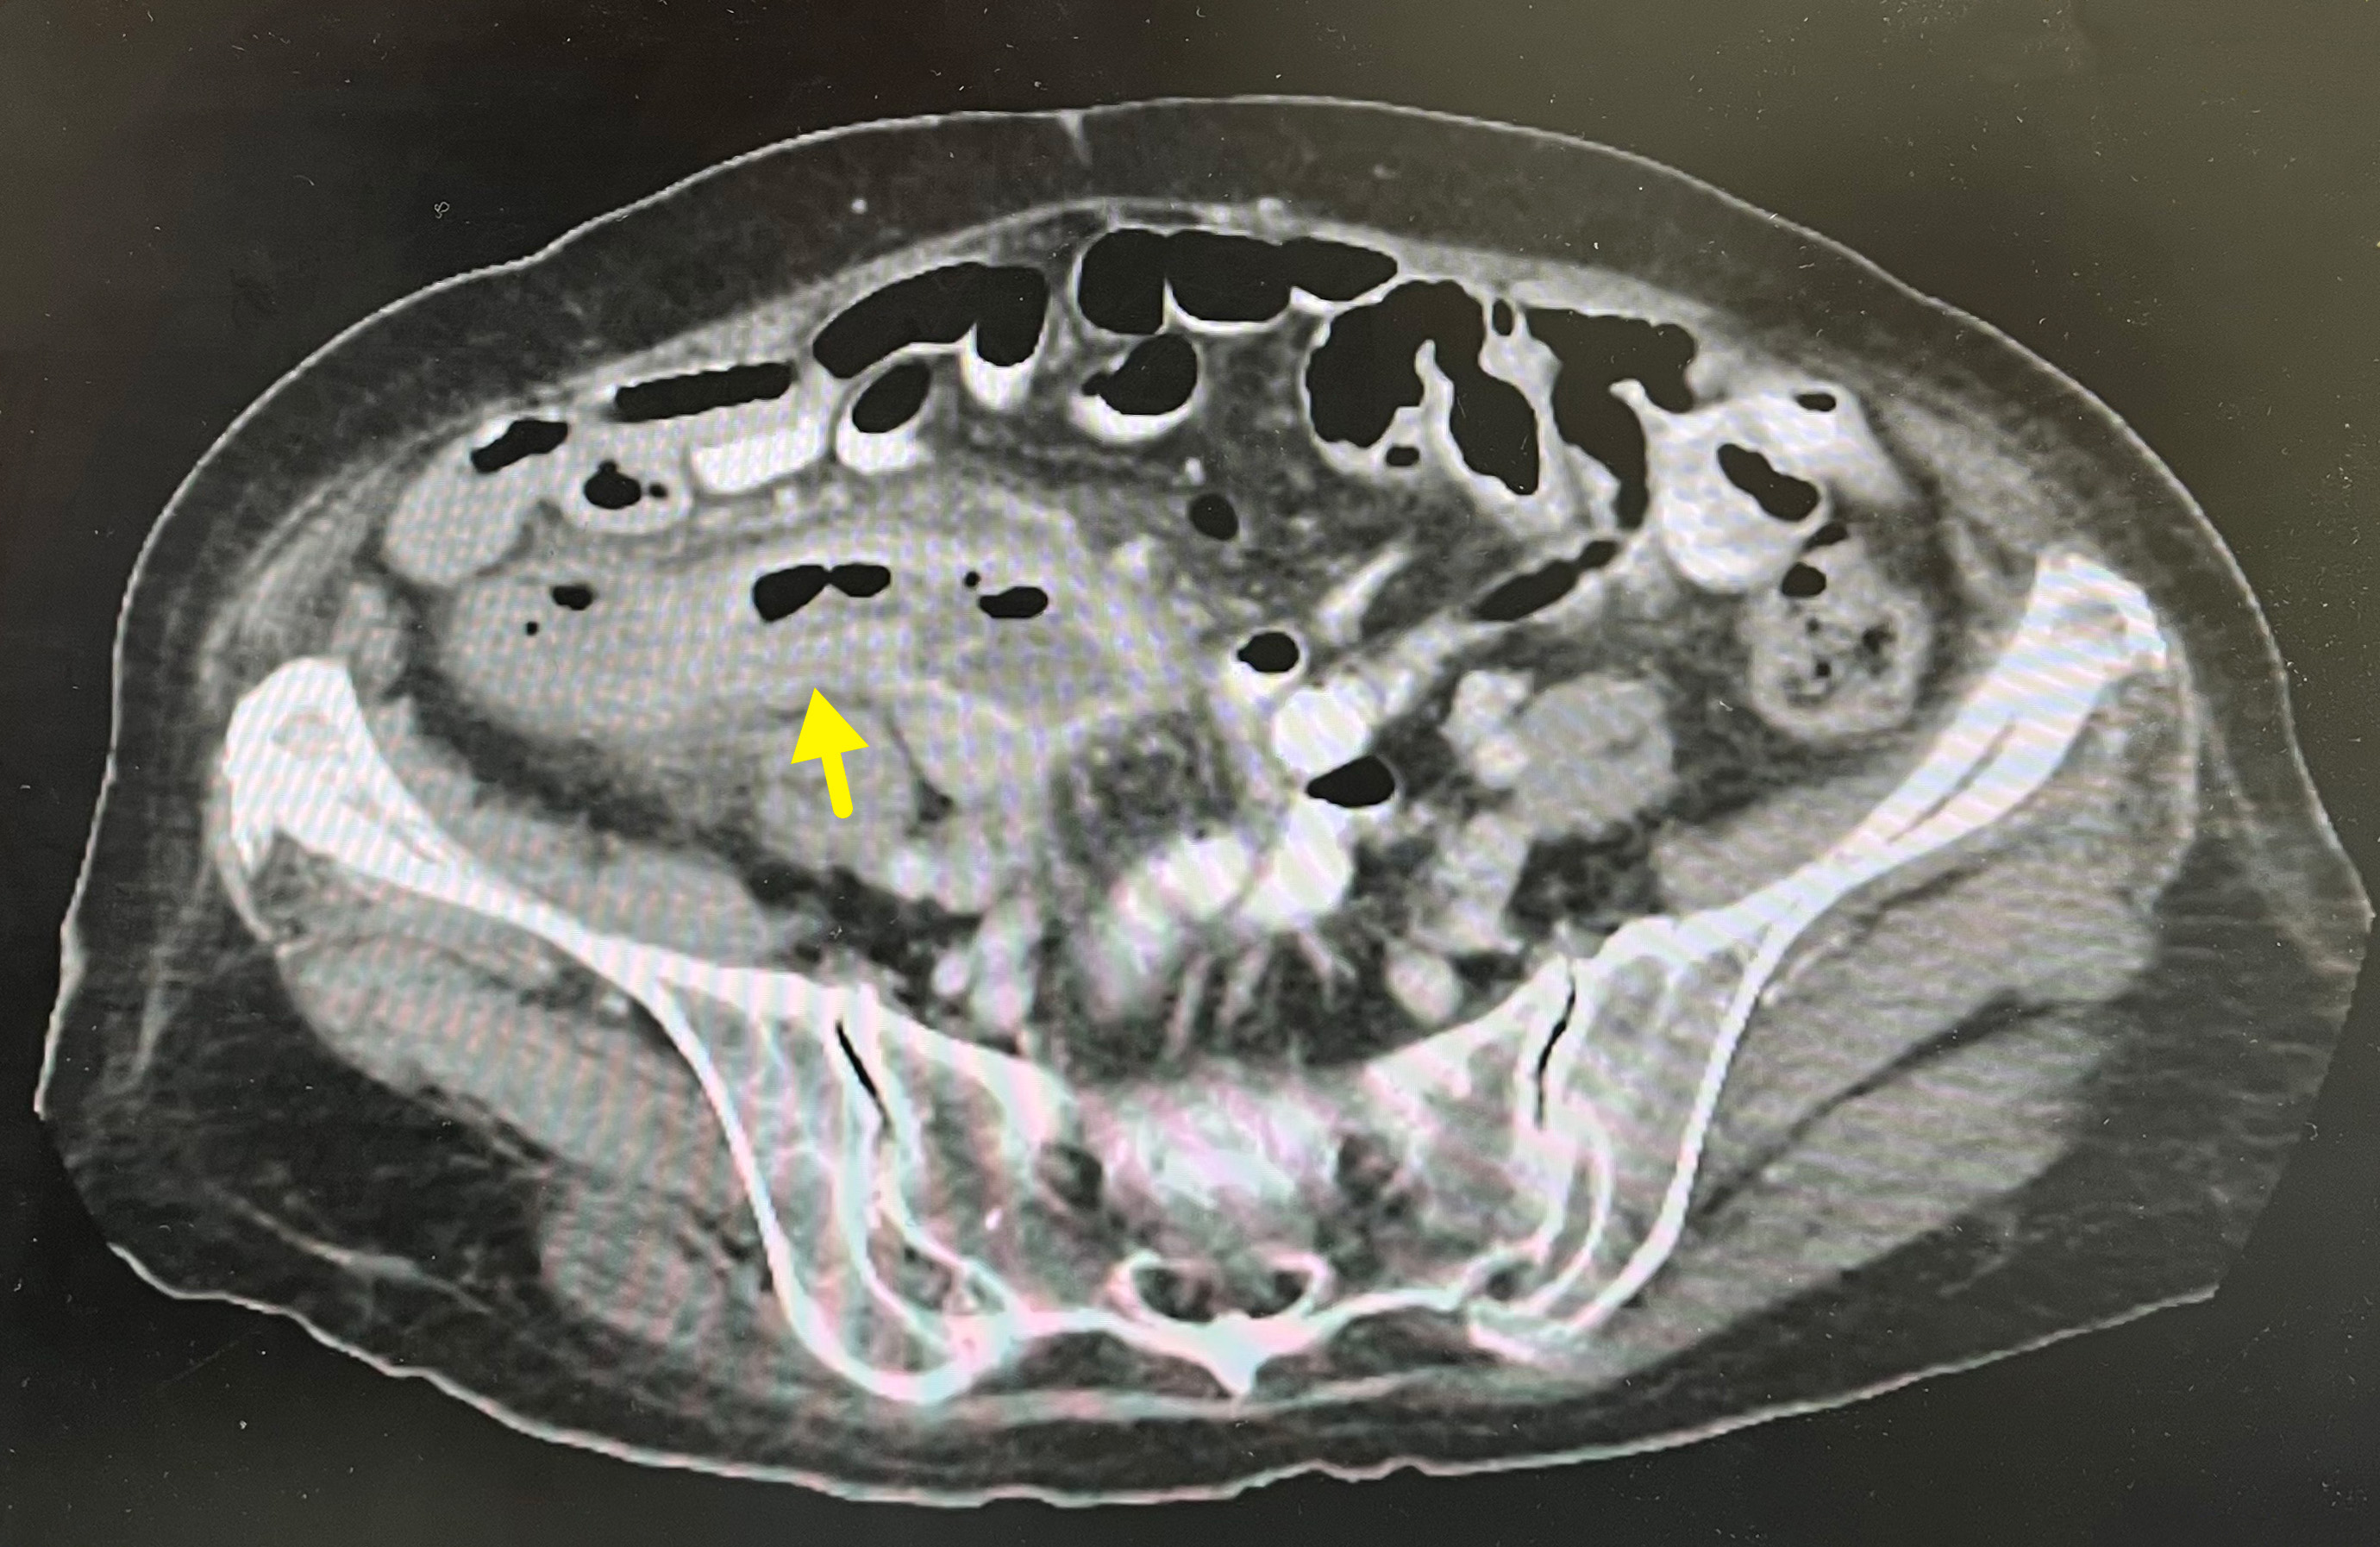

圖:台中榮總提供